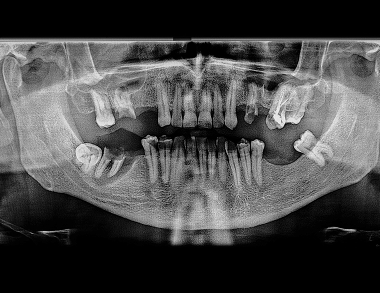

Dental X-rays are essential diagnostic images that use low levels of radiation to capture detailed pictures of your teeth, roots, and jawbone. They reveal hidden structures and problems not visible during a regular oral exam.

Common types include bitewing X-rays to check for cavities between teeth, periapical to view the entire tooth root, and panoramic images for a broad overview of the jaws, teeth, and joints.